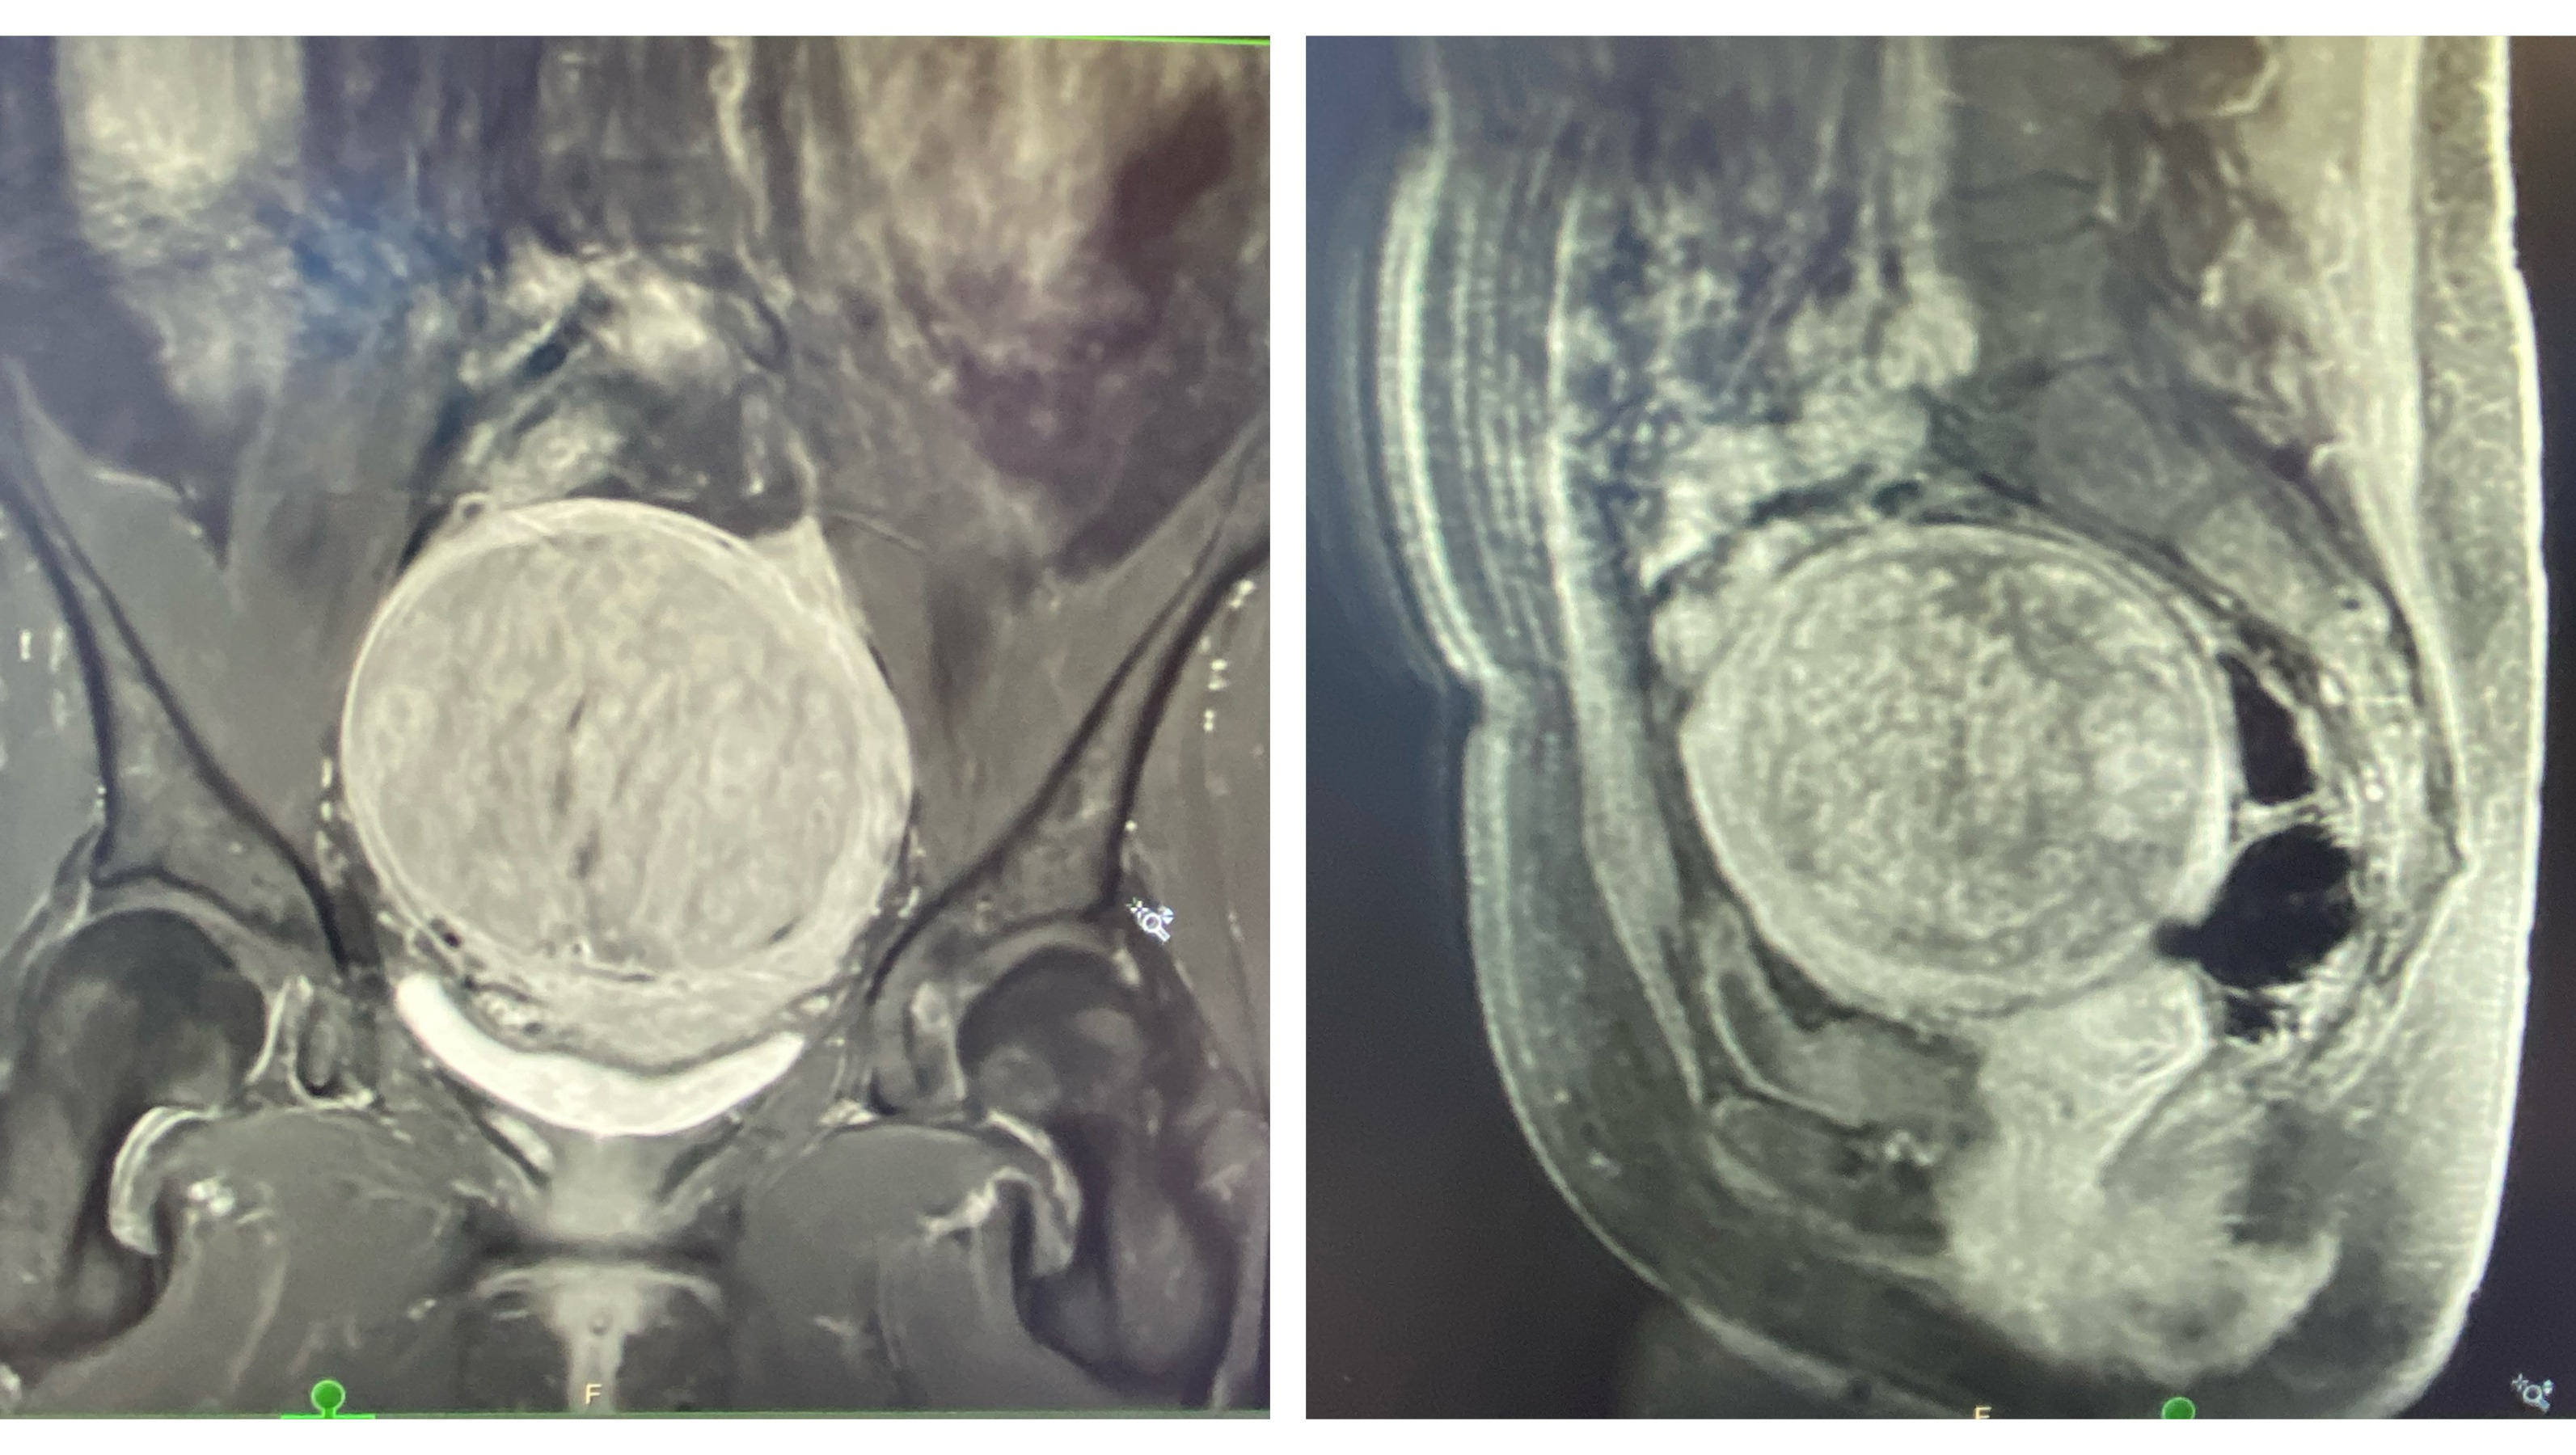

At the end of March, I will undergo a routine but complex open surgery to remove a very large (10cm) fibroid tumor from my body which I have named "Gladys", as pictured.

Yes, it's that large white circular thing that looks like a Full Moon. Gladys, the 'grapefruit', is lodged in my lower abdominal area, blocking all sorts of fun bodily functions. "Gladys" has got to GO!